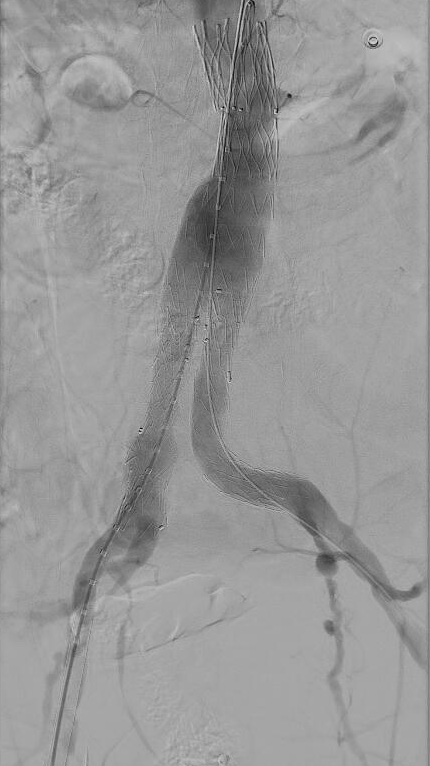

Se contacta con UCI iniciando protocolo de transfusión masiva y drogas vasoactivas y se traslada a Hospital de referencia para tratamiento definitivo por cirugía vascular, colocándose una endoprótesis.